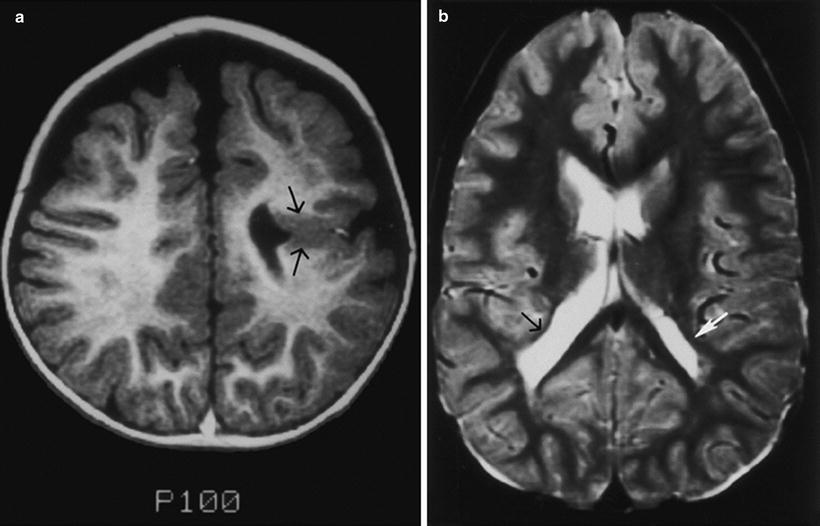

Cerebral hemispheric abnormalities associated with optic nerve hypoplasia. (a) Axial T1-weighted inversion recovery MR image demonstrating schizencephaly in patient with optic nerve hypoplasia. Schizencephalic cleft (arrows) consists of abnormal band of dysmorphic gray matter in left cerebral hemisphere extending from cortical surface to lateral ventricle. (b) T2-weighted axial MR image demonstrating asymmetrical periventricular leukomalacia, worse in right hemisphere (left side of picture), in child with optic nerve hypoplasia. Note enlargement and irregular contour of posterior aspect of lateral ventricle. Black arrow denotes loss of posterior periventricular white matter, with direct apposition of cortical gray matter to trigone of lateral ventricle. White arrow indicates greater volume of posterior periventricular white matter in the left hemisphere. With permission, from Brodsky and Glasier [58]. Copyright 1993, American Medical Association.